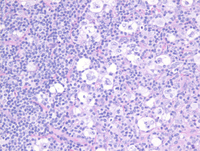

High power H&E images

At higher power, there are scattered large cells with clear cytoplasm and central nuclei present in a background of small lymphocytes. Further examination demonstrates that the large cells are either mononuclear or multinucleated variants of Hodgkin/Reed-Sternberg cells, also called "lacunar cells". Lacunar cells represent an artifact of formalin fixation due to retraction of the cell membrane as a result of formalin fixation.